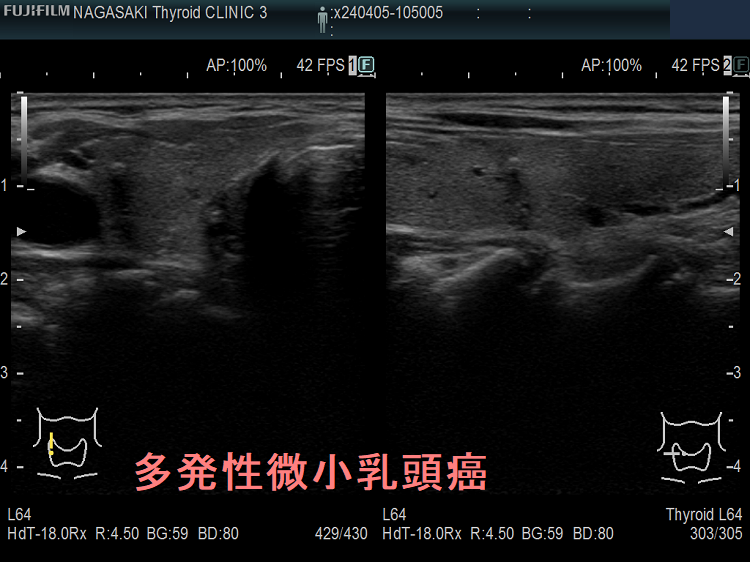

多発性の甲状腺微小乳頭癌

多発性の甲状腺微小乳頭癌は、リンパ節転移しやすいとされます(Am J Surg. 2014 Sep;208(3):412-8.)。

- 海外では、①両葉多発性の場合、②甲状腺癌の家族歴(遺伝性)がある場合、甲状腺微小乳頭癌であっても甲状腺全摘が推奨されます[アメリカ甲状腺学会(American Thyroid Association:ATA)やヨーロッパ分子癌学会(European Society of Molecular Oncology:SMO)のガイドライン](Thyroid. 2016 Jan;26(1):1-133.)(Ann Oncol. 2019 Dec 1;30(12):1856-1883.)(下記)